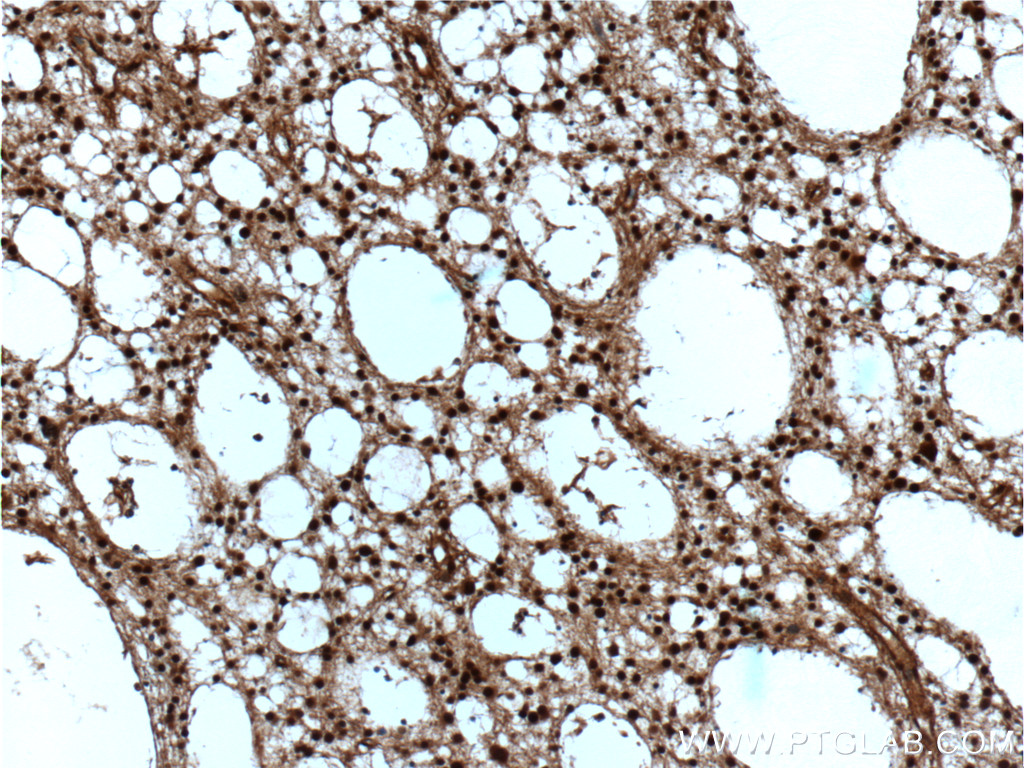

| Positive IHC detected in | human gliomas tissue, human colon cancer tissue, human lung cancer tissue Note: suggested antigen retrieval with TE buffer pH 9.0; (*) Alternatively, antigen retrieval may be performed with citrate buffer pH 6.0 |

| Immunohistochemistry (IHC) | IHC : 1:100-1:400 |